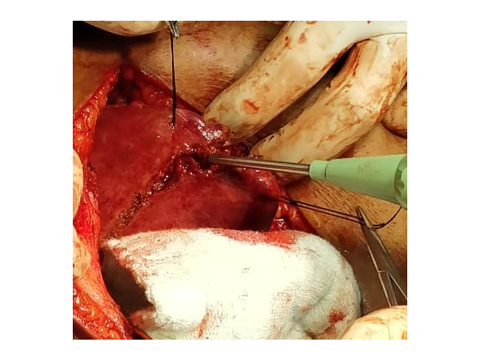

We have state of the art operating theatre with advanced surgical equipments. We have a Karl Storz Spies advanced HD laparoscopy operating system in addition to a 3 chip laparoscopy. We have installed advanced vessel sealing devices like Gen 11 harmonic scalpel, Ligasure from Valley Lab & Argon plasma coagulator. There is a recent addition of Cavitron Ultrasonic Aspirator (CUSA) system into our surgical armamentarium. We have the most recent powered Echelon endo-stapling devices. In addition to all these we have a constant supply of various types of advanced stapling devices for GI surgeries. Our endoscopy machines are having high definition with FICE Technology. Last but not the least we have semi flexible Ureteroscopy for managing common bile duct stones.

ARGON PLASMA COAGULATOR